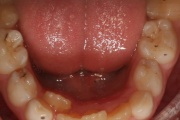

Koonilise kujuga lisahammas ülemiste tsentraalsete lõikehammaste vahel.

Suulaepoolt lõikunud koonilise kujuga lisahammas